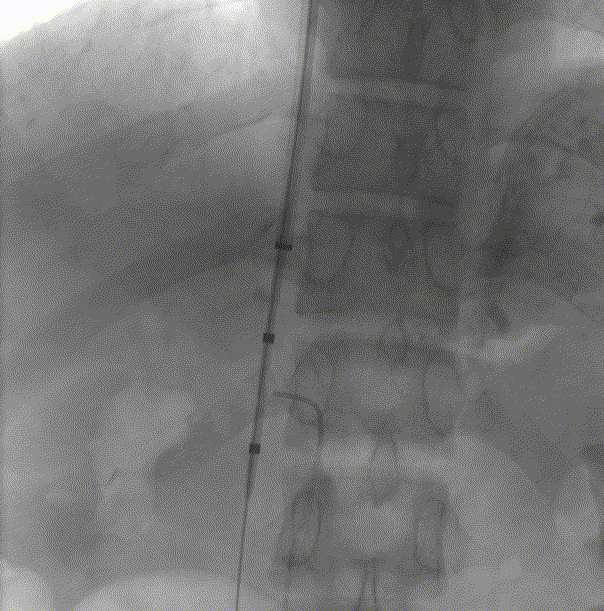

5. 穿刺成功后直接跟入泥鳅导丝至下腔静脉。

6. 经颈静脉置入抓捕器,引出泥鳅导丝,建立贯穿轨道。

7. 经肠系膜导管置入8mm球囊,扩张后将10F鞘管自下腔静脉引入门静脉远端。